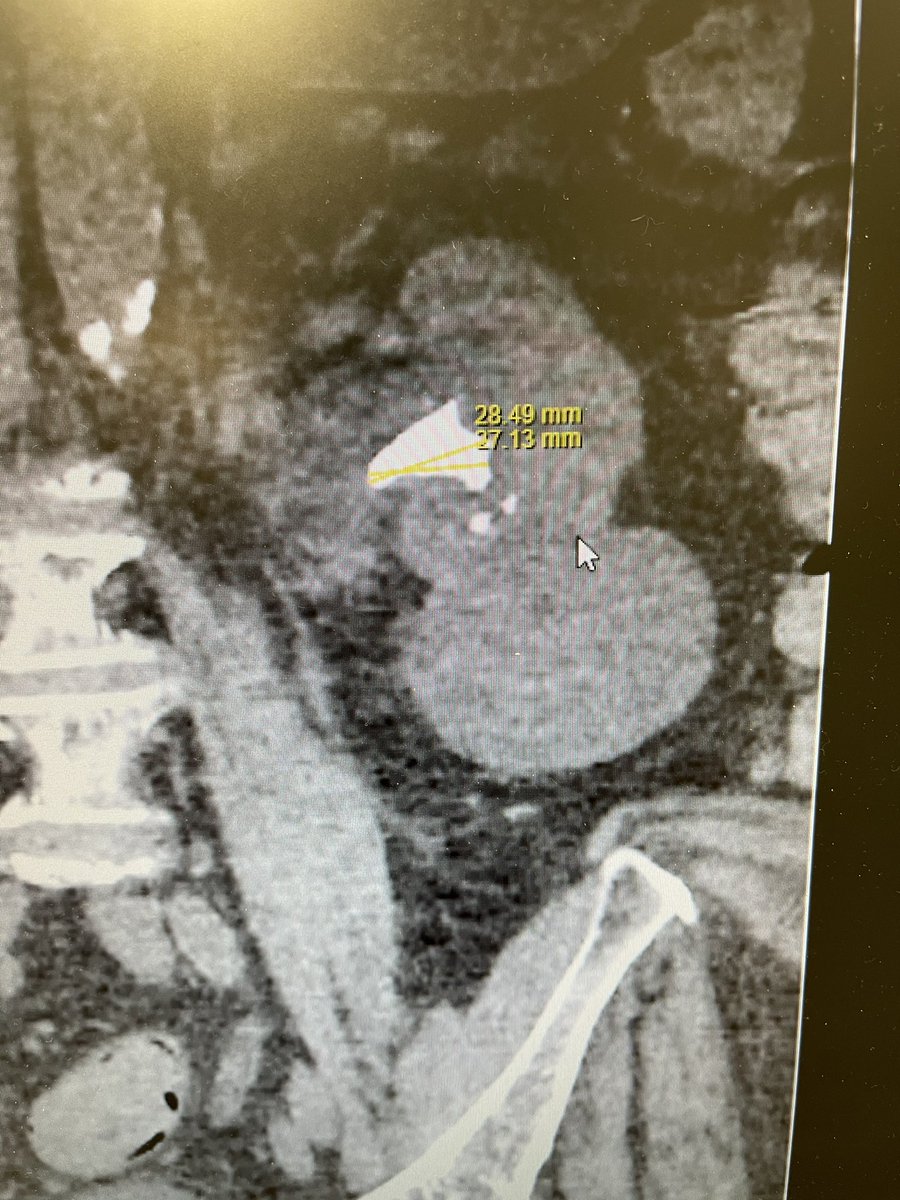

What a great day. Team urology at Whiston Hospital - trialled the Olympus Soltive thullium laser on a 2.8cm stone this morning. Lasering time only 45 mins! Stone dusted completely. Thank you Amanda and Joe from Olympus UK.

@sthknhs @OlympusUK #endourology #stones